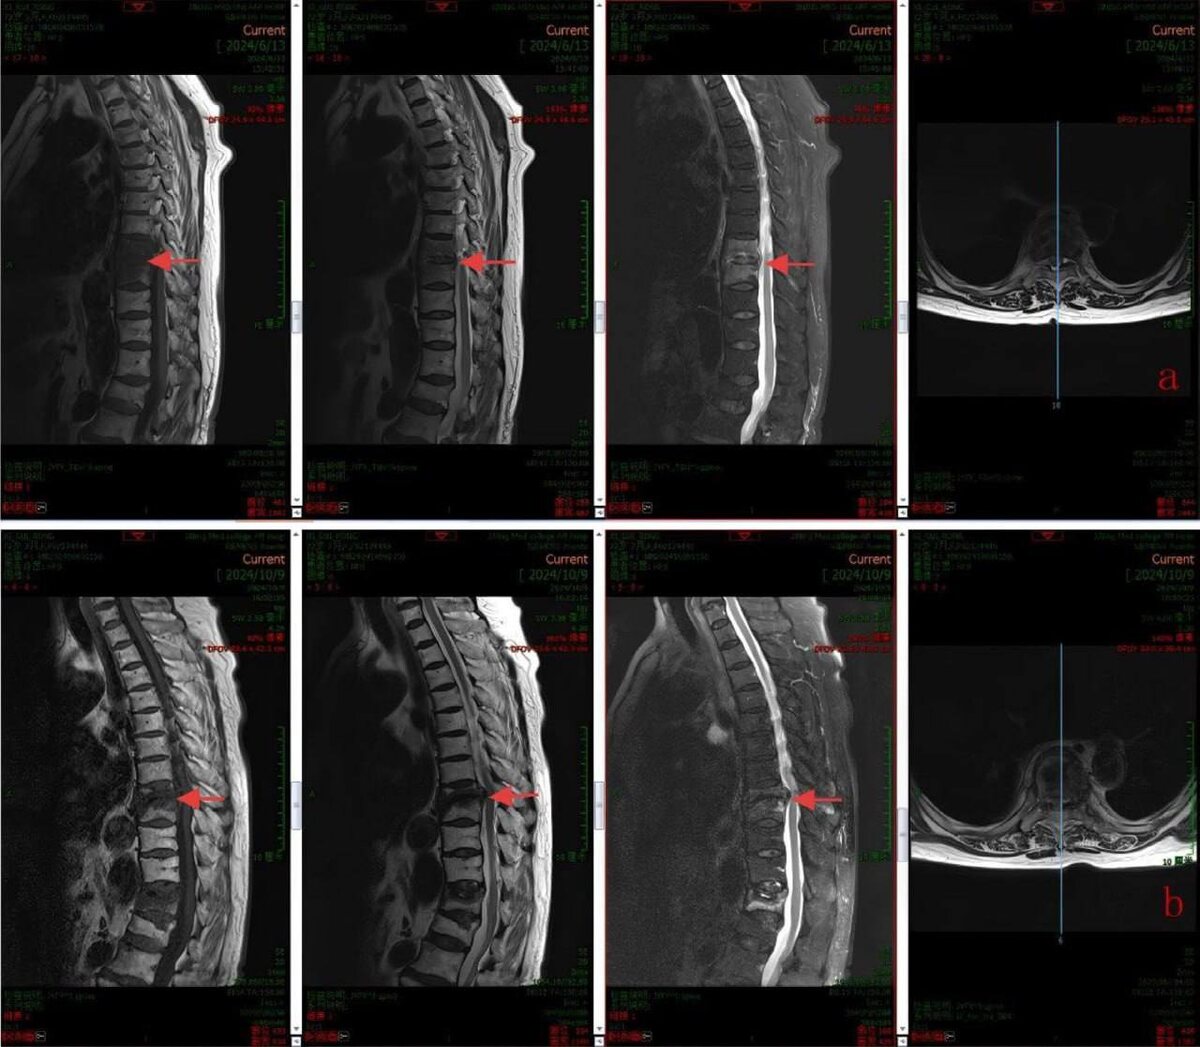

Перед вами реальная история нашей пациентки, 72-летней Людмилы Петровны.

Месяц ада: температура под 40, дикая боль в спине, которая не снимается. Обычные антибиотики давали лишь временное облегчение. Казалось, что это навсегда.

2️⃣ Подобрали «ключ» к лечению. Даже правильный антибиотик не работал по стандартной схеме. Наши коллеги, врачи-инфекционисты использовали метод продленной инфузии — препарат вводился медленно, 3 часа, в повышенной дозе. Это позволило ему постоянно «атаковать» инфекцию в кости. Результат — температура упала, боль отступила, а маркер воспаления (СРБ) снизился в 9 раз.

Главный итог: Мы победили тяжелейший гнойный спондилит без операции, индивидуально подобрав терапию. Пациентка избежала инвалидности и вернулась к жизни.